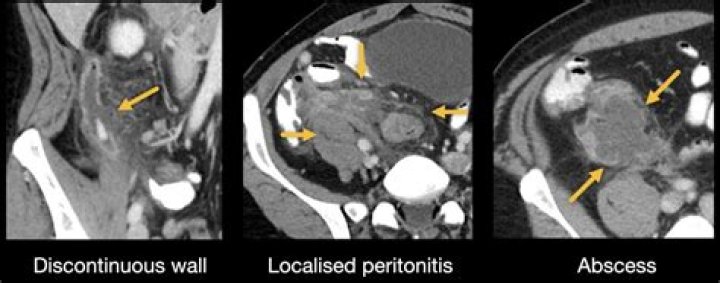

Score: 5/5 (69 votes) Doctors can use an abdomen CT scan to diagnose a range of different cancers that can happen in that part of your body. This include...